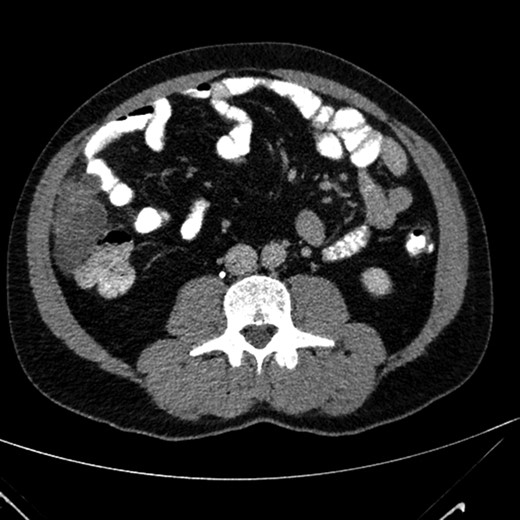

A 40-year-old Caucasian male, a past medical history of smoking, complaining from 5 years of occasional abdominal discomfort started having an acute, stinging pain in the right upper abdomen. A blood sample was taken that showed a smoldering increase of the transaminases and C-reactive protein of 22 mg/L. He was investigated in the outpatient setting with an abdominal ultrasonography that revealed a polycystic lesion of 9 cm of diameter in the right flank. He was than referred to our Hospital, where the physical examination was completely silent. A contrast enhanced CT scan of the abdomen revealed a polylobate hypodense formation, with multiple thin internal septa which are enriched after contrast (dimension 83 × 43 × 61 mm) (Figs 1 and 2). Radiologist posed differential diagnosis among peritoneal lymphangiomatosis, enteric duplication cyst and—even if less likely in a male without history of past abdominal surgery—benign multicystic peritoneal mesothelioma. After multidisciplinary discussion we proceeded to an exploratory laparoscopy that confirmed the presence of multiple cystic lesions of the peritoneum, some interesting the omentum, with a weak adherence with the ascending colon (Figs 3 and 4). We performed a complete excision of the neoformation, with free margin on omental fat. A small lesion of the colonic serosa was treated with a prophylactic continuous suture with Vycril 2-0. The postoperative course was uneventful ant the patient was discharged after 2 days without complications.

Contrast enhanced axial image that show the presence of a polylobate hypodense formation, with multiple thin internal septa.